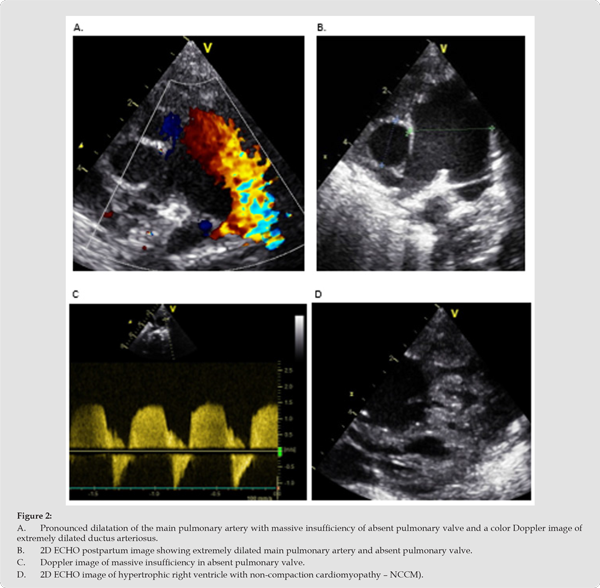

Re-catheterization at the age of 14 months shows a recurrent aneurysm of the right branch of the pulmonary artery (Figure 6 A & B, pat. 2), and a stenotic process with insufficiency at the junction of the conduit (Figure 6C & D, pat. 2). The images show a still hypoplastic LPA and a predominant flow of contrast through the right lung. Patient 4 had a ligature of tortuous (wide) DB at the age of 7 days, and after atelectasis of the left lung, due to compression of the RPA on the left bronchus, at the age of 3 months, a LeCompte manoeuvre was performed and a 12 mm Contegra conduit with a valve was implanted. He is currently recovering well with hope for a cure (Table 2). In the further course of the disease, we expect the main problems to be due to non-compact right ventricular cardiomyopathy. Fluorescence in situ hybridization (FISH) was performed in all patients to exclude deletion syndrome (q22.11) because it is believed that the described changes belong to etiopathogenetic conotruncal anomalies, but no deletion was found in our patients.